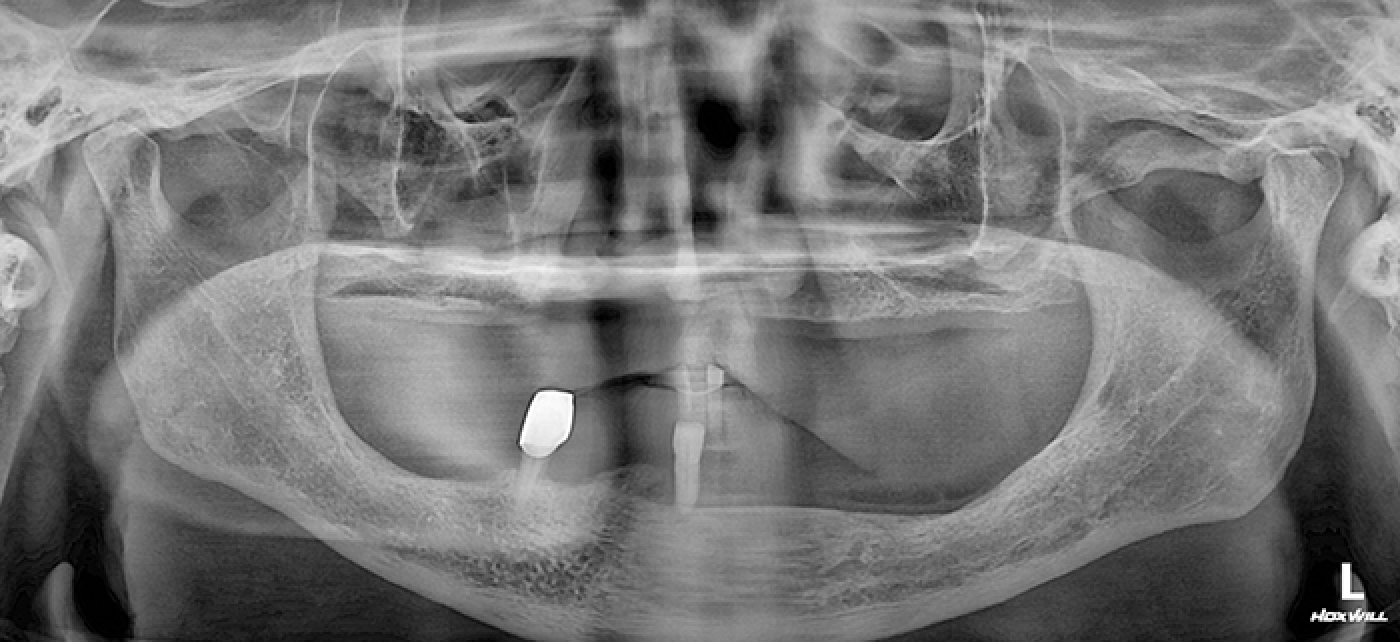

• 임플란트 전

Before

2021년 07월

• 수술 전 x-ray

치아상태 : 무치악 / 타병원에서 임플란트, 임플란트 틀니 진행 불가 판정받아 틀니 5년째 사용중

특이사항 : 고지혈증, 당뇨